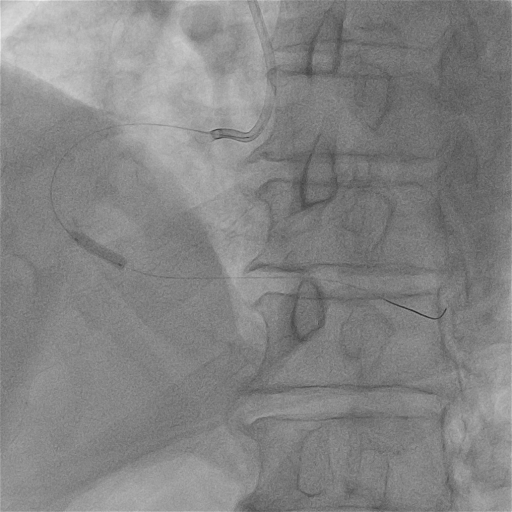

ROTA 1.5Burr首次旋磨

1.5mm旋磨头分段式旋磨RCA近、中、远段病变,轻进快退“啄米式”充分旋磨近端后再逐步前进,旋磨头顺利通过近中段病变并对病变处进行充分打磨。

1.5mm旋磨头通过中远段病变,对钙化病变充分进行旋磨抛光。